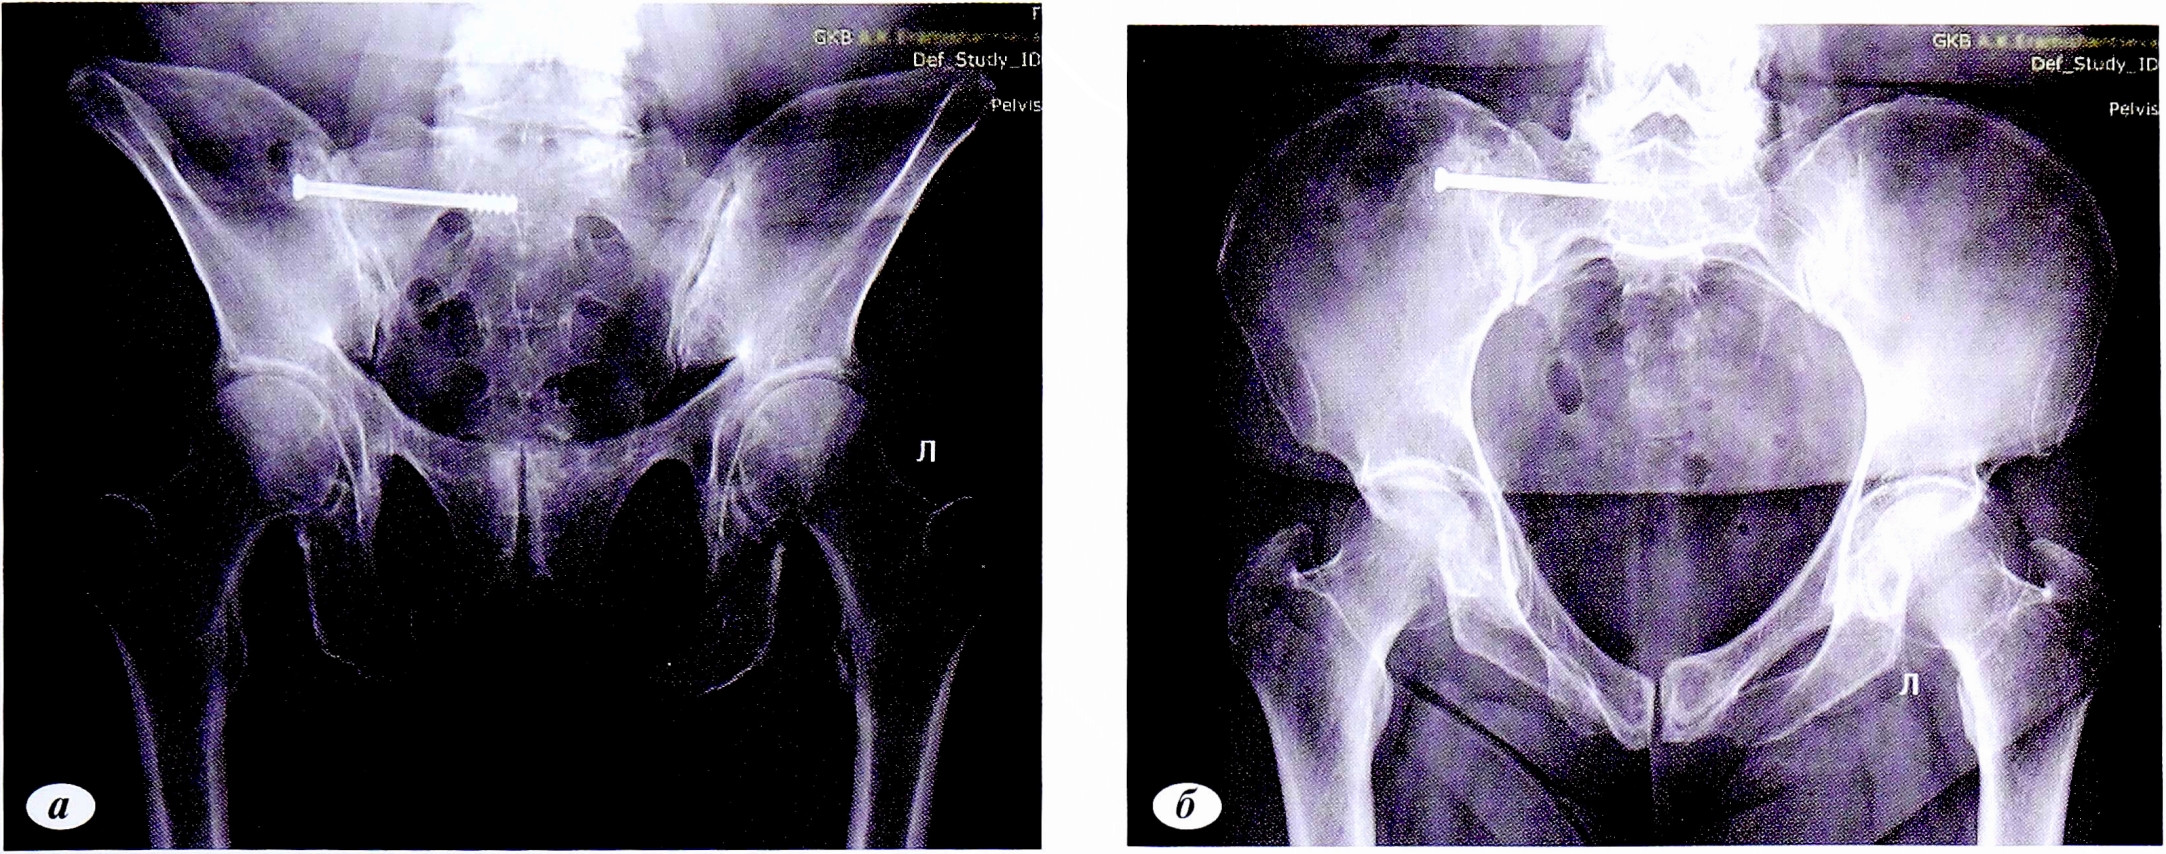

Клинический пример 2. Пациент Л.,70 лет. Травма в результате падения с высоты собственного роста. За медицинской помощью обратился на следующий день после травмы в связи с нарастанием болевого синдрома.

При обследовании выявлен перелом лонной и седалищной костей слева со смещением отломков. На фоне симптоматической терапии, профилактики тромбоэмболических осложнений пациент активизирован с дополнительной опорой, дозированная нагрузка на левую нижнюю конечность. Выписан на 3-и сутки.

Отдаленные результаты через 12 мес: на контрольных рентгенограммах определялись консолидированный перелом лонной кости, ложный сустав ветви седалищной кости (рис. 4). По шкале S. Majeed — 82 балла, по тесту «Timed up & go» теста 11 с.

Рис. 4. Пациент Л.,70 лет. Контрольные рентгенограммы через 12 мес. Консолидированный перелом лонной кости, ложный сустав ветви седалищной кости, а — проекция: выход из таза; б — проекция: вход в таз.

Fig. 4. Control radiographs of a consolidated fracture of the pubic bone, nonunio of the sciatic branch, a — outlet view; б— inlet view.

Использует трость при ходьбе более часа (рис. 5).